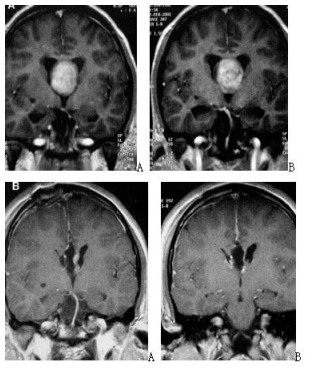

Neurosurgical Oncology Ward 3Neurosurgical Oncology Ward 3 (Middle-line skull base tumors and neuroendoscopy) Specialized features The Neurosurgical Oncology Ward 3 is characterized by the clinical application of neuroendoscopic technology. The annual number of neuroendoscopic surgeries exceeds 1200, and the quantity and quality of neuroendoscopic surgeries are leading domestically and internatio…